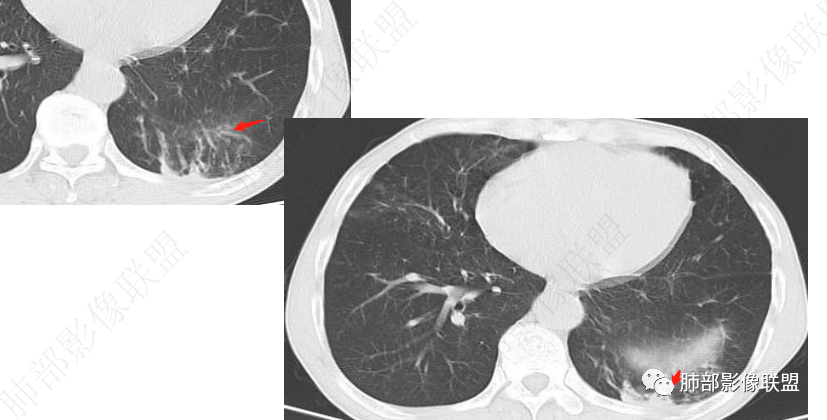

谢加平:

左肺下叶体积缩小,其后基底段斑块病灶,边缘清,与胸膜平行,似楔形状,有平直征,不均匀强化,内见血管造影(需薄层确认),周边索条纤维灶及小树Y,另左肺下叶支气管壁增厚,方向炎性肉芽肿,或球形肺炎,与淋巴瘤鉴别,经皮肺定位穿刺活检。

3.影像表现双肺可见多发斑片状,条索及结节状高密度影,界不清,树芽征(+),考虑肺结核问题不大。左肺下叶背段结节病灶相对另类,应当警惕结核伴肿瘤,如腺癌。该病灶边缘有刀切征,未见典型分叶毛刺,结合周围有卫星灶,胸膜增厚粘连,可疑反晕,边缘有少许的磨玻璃样改变、较模糊,病灶周围有条索、树芽,相对强化较轻微,一元论考虑肺结核可能性大。腺癌如伴有磨玻璃多为中心实性成分周围为磨玻璃成分,且病灶膨隆为主、可见分叶、毛刺、胸膜凹陷、血管集束,脐凹征等征象,本例有轻微胸膜长线牵拉凹陷但其余肺癌常见恶性征象均不明显,且出现边缘平直等明显指向良性病变的征象。

左肺下叶片状影,边界不清,强化明显,更符合感染性炎性病变。